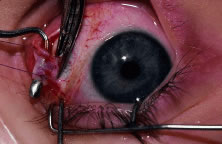

This procedure is recession of the right medial rectus muscle. The eyelids are separated with a Barraquer open-blade wire eyelid speculum (Fig. 8). The open-blade design provides more room for exposure and makes it easier to pass the suture needles, especially in small children or when large recessions are performed. The globe is grasped with a Lester forceps at the limbus. It is best to grasp the limbus with the forceps held perpendicular to the globe and then to position the forceps so that they are rotated and lie tangential to the globe. Forced ductions are performed to detect any restriction of movement of the globe (Fig. 9).

|